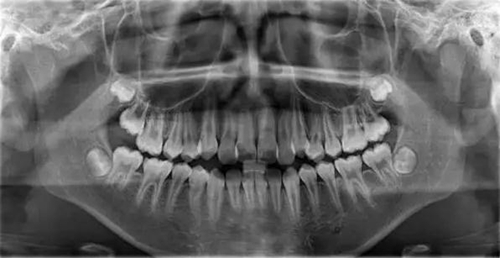

1500866161_694151.jpg1500866311_947305.jpg

此病例主要考慮的是垂直骨面型,矢狀骨面型,前牙覆合覆蓋及尖牙關(guān)系,側(cè)貌